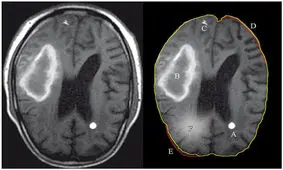

در این اینفوگرافی مهمترین نشانه های سرطان ریه را بشناسید.